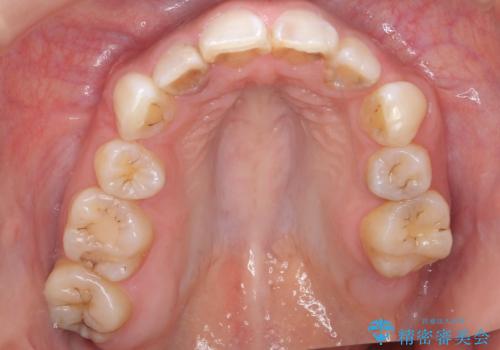

- 上の前歯の色と隙間を気にされ、来院された患者様です。

精査したところ、右上の側切歯(右上2)は神経が死んで変色しており、左上の側切歯と犬歯の間に2mm程度の隙間を認めました。

学生時代に舌側矯正をされており、通院が大変になり治療を途中でやめてしまったとのことでした。

矯正せずに早く治したいという強いご希望により、セラミッククラウンによる補綴治療(上顎両側2の2本)を行いました。

- ¥396,000 (根管治療・土台×1本、仮歯・クラウン×2本) ※税込費用は治療当時の料金となります